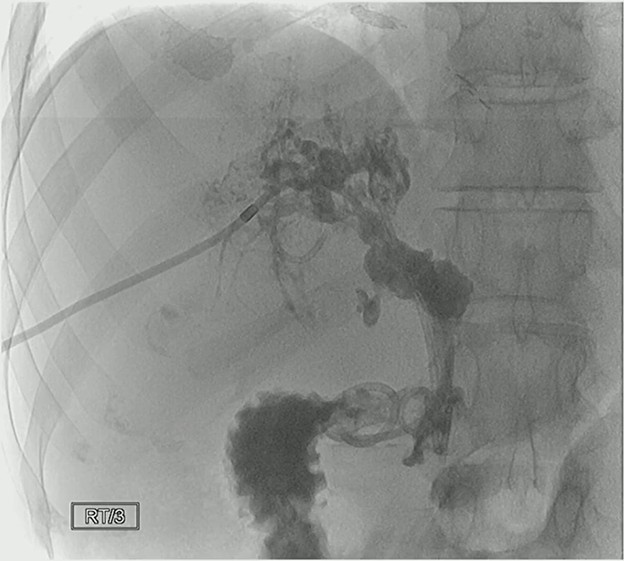

A stark example of what PSC can look like for a patient out in the world untreated for more than a decade, take note of key cholangiographic features, including:

- Multifocal strictures—Numerous short, irregular narrowings along intrahepatic and extrahepatic bile ducts.

- Beaded appearance—Alternating pattern of strictures and dilations creates a “string of beads” look.

- Pruning—Loss of smaller peripheral ducts; distal branches become fewer and less visible.

- Irregular walls—Bile ducts often have rough, irregular contours (not smooth like normal ducts).

- Dominant strictures (sometimes)—A single, especially tight narrowing in a major bile duct, often the common bile duct or hepatic ducts.